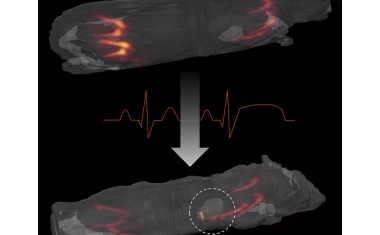

Neutrophile Granulozyten spielen bei vielen Erkrankungen, die mit Entzündungen einhergehen, eine Schlüsselrolle.